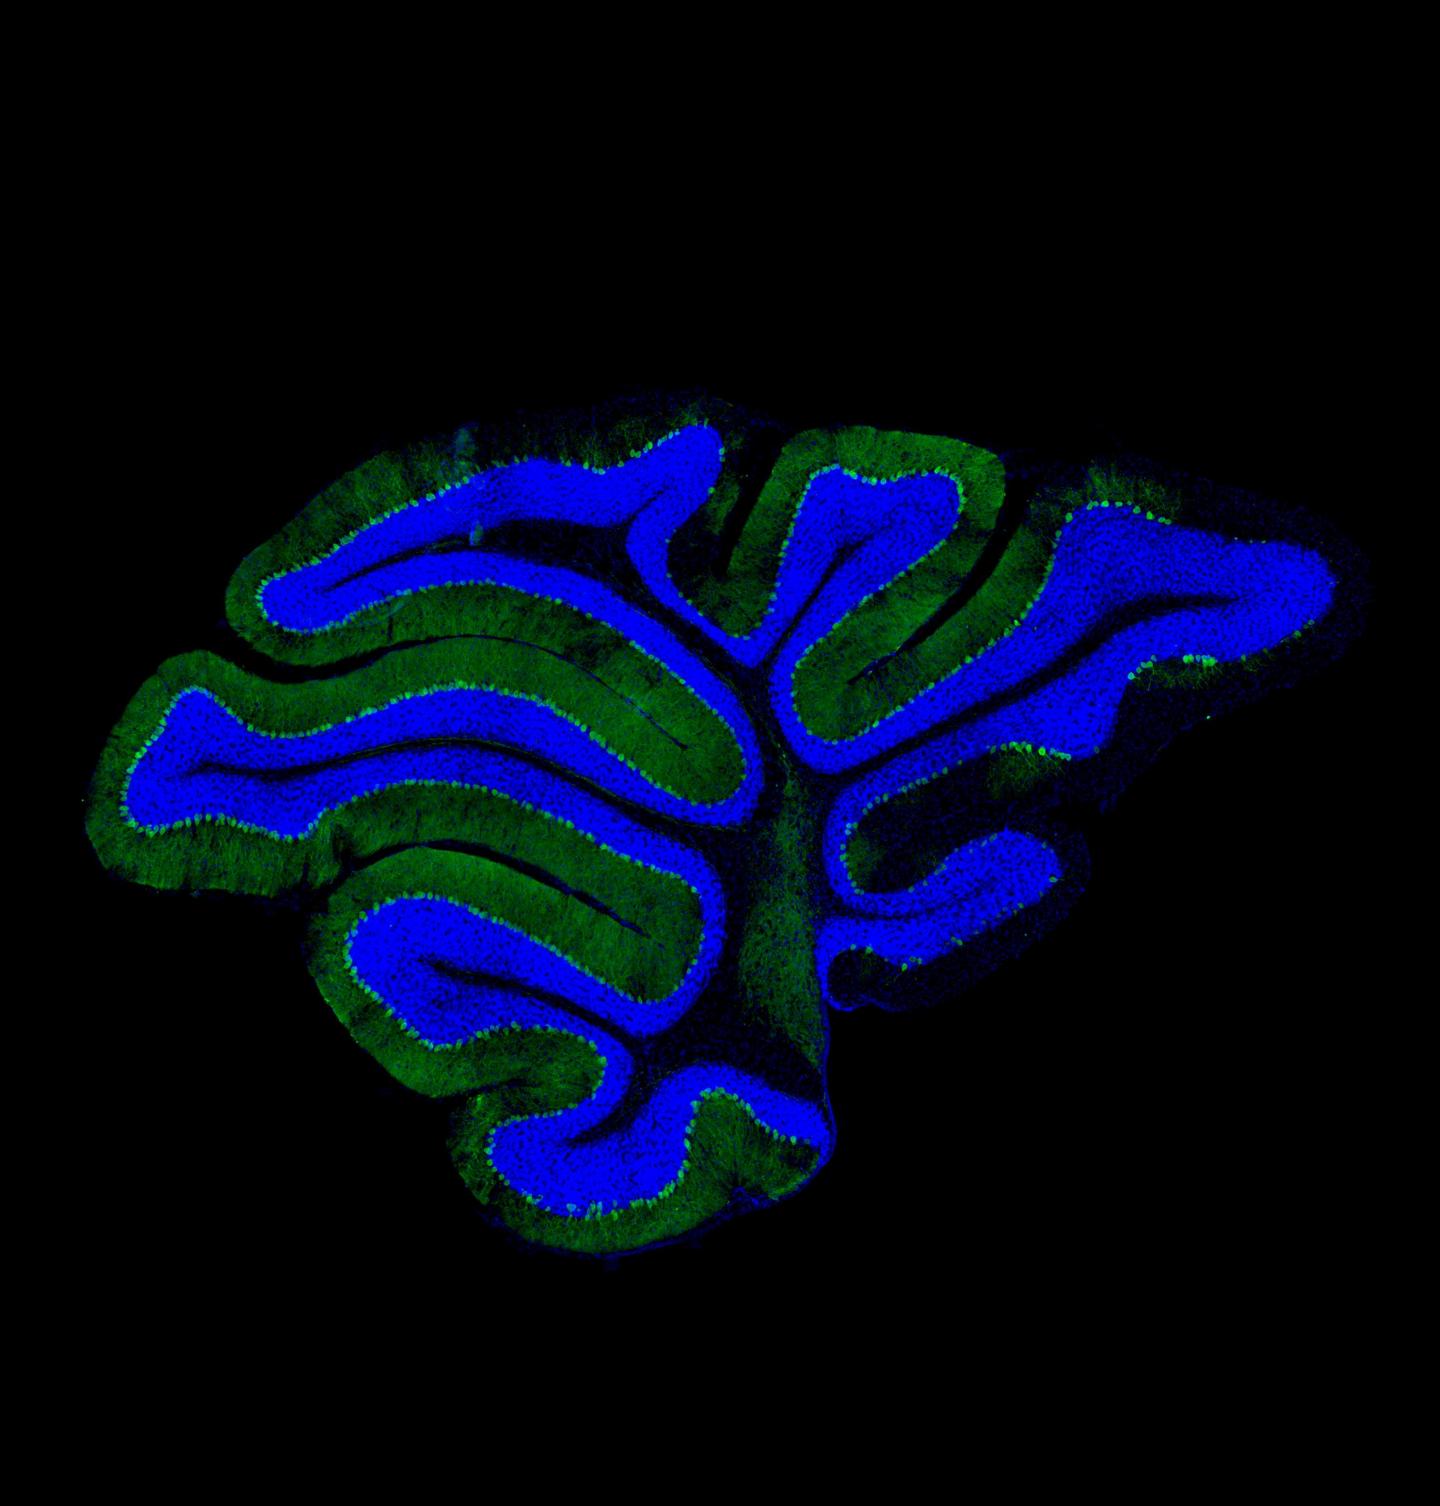

Disabling a part of brain cells that acts as a tap to regulate the flow of proteins has been shown to cause neurodegeneration, a new study from The University of Manchester has found.

The research, which was carried out in mice, focused on the Golgi apparatus -- a compartment inside all cells in the body that controls the processing and transport of proteins. It is fundamental for the growth of the cell membrane and also for the release of many types of proteins such as hormones, neurotransmitters and the proteins that make up our skeletons.

Working with Chinese colleagues, the Manchester researchers examined the role of the Golgi apparatus in neurons, or brain cells, and found that mice in which the apparatus was disabled suffered from developmental delay, severe ataxia, and postnatal death.

The paper, 'Loss of the golgin GM130 causes Golgi disruption, Purkinje neuron loss, and ataxia in mice', was published in PNAS . doi: 10.1073/pnas.1608576114